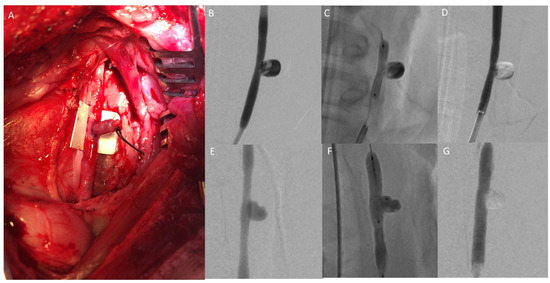

2.2. Animal Model

5.4. Animal Model Testing